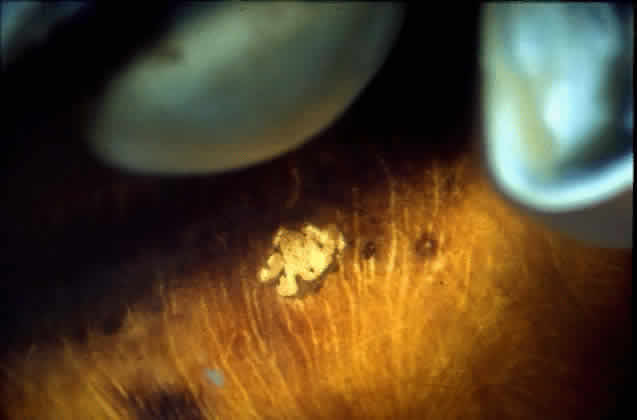

The funduscopic appearance of ischemic lesions in the choroid has been recognized since the early 19th century. In 1904, Elschnig67 described areas of circumscribed secondary RPE loss (Elschnig's spots), which are now recognized to be signs of ischemic infarcts arising from acute occlusion of the choriocapillaris or precapillary choroidal arterioles (Figs. 32, 33, and 34). Multifocal acute ischemic choroidopathy results from acute ischemic lesions of small choroidal arterioles, whereas geographic choroidopathy is due to an occlusion of larger choroidal arterioles or small arteries.47Triangular or wedge-shaped choroidal lesions appear to be three-sided, the apex pointing posteriorly and the base anteriorly. They are believed to represent evidence of occlusion of larger choroidal vessels. Occlusion of the long or short posterior ciliary arteries or their branches results in triangular defects. Triangular defects caused by obstruction of the short posterior ciliary arteries are more numerous, more irregular, and usually smaller. If the triangles become confluent, they may produce hemiatrophy of a quadrant.47,68

Fig. 32. Area of peripheral choroidal ischemia in gross specimen.